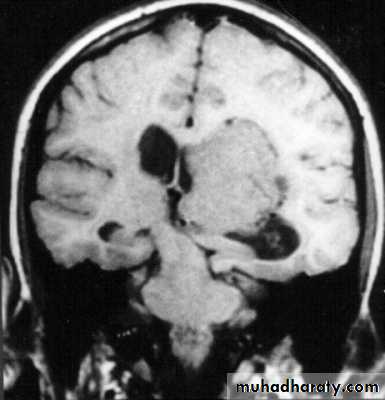

Etiology:1. Localized masses like:

a. Haematomas: epidural, subdural, and intracerebral.

b. Neoplasms: gliomas, meningiomas, and metastases.

c. Abscesses (brain abscesses).

d. Focal oedema due to traumas, infection, and tumours.